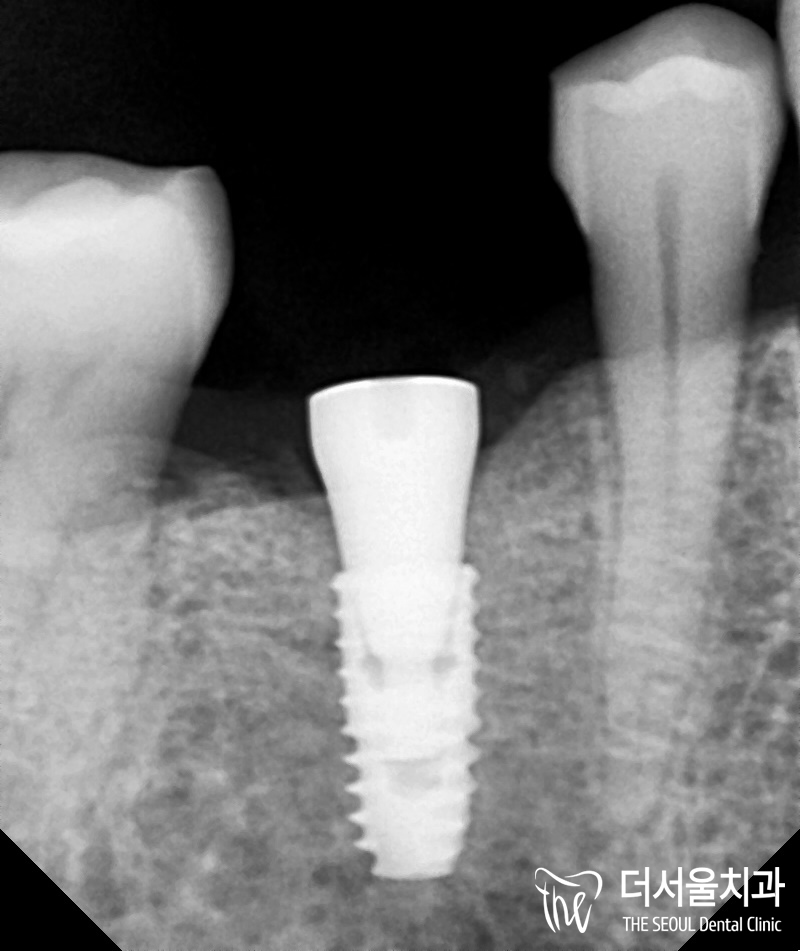

픽스처(고정체) 식립 수술 후,

뼈와 결합이 잘 이뤄진 것을

볼 수 있습니다.

이제는 어버트먼트(지대주)와

크라운을 씌워주면 되겠네요.

잔존 유치 가 있었던 45번 자리에

임플란트 식립이

잘 이뤄진 것을 볼 수 있습니다.